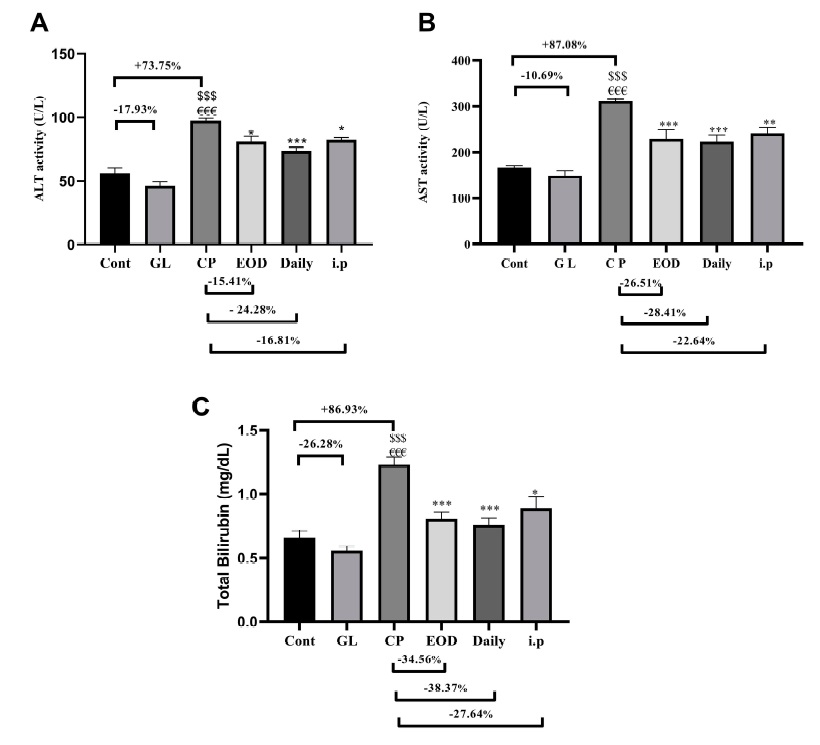

After 10 days, it can be seen that cisplatin will increase the hepatitis index and total bilirubin level in the rat’s serum. These are all signs of hepatocellular injury. But if Ganoderma lucidum is involved at the same time, the increased value can be reduced a lot (Figure 1).

Data Source/Drug Des Devel Ther. 2020; 14:2335-2353.

Figure 1 Effects of cisplatin and Ganoderma lucidum on liver injury indicators